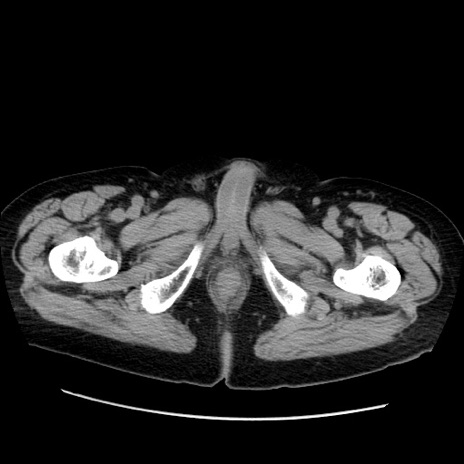

冠状断像